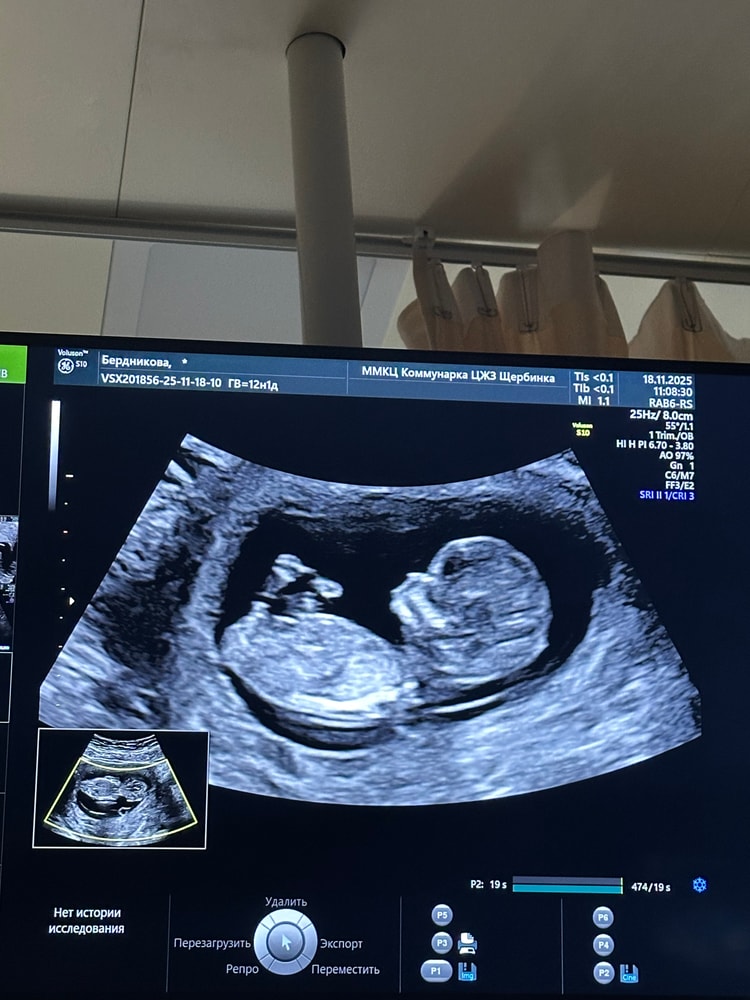

Все отлично. Камень с души. Зайчик полностью здоров. Носик маловат, но это в маму пошел, врач успокоила 😁

Риски по-прежнему низкие, развивается, как по книжке. Маленький, красивый и здоровый сынулка.

Ну, и напоследок показал все свое достоинство🤣

19+3 - мы идем дальше💙